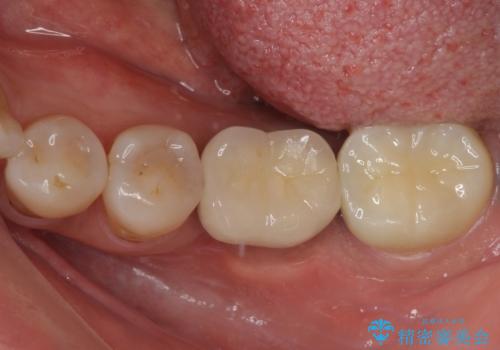

- 目立つ銀歯やむし歯、前歯のデコボコを気にして来院された患者様です。

むし歯治療は、症状のある歯を矯正治療前に処置し、概ね歯列が整ったところで残りのは全て処置し、最後にインビザラインで歯列を仕上げることで、無駄なく治療を進めて行くこととしました。

セラミック治療の注意事項(リスク・副作用など)

- 天然歯を削ります

- 硬い素材は天然歯を傷つけてしまう場合があります

- かみ合わせや歯ぎしりが強すぎる方はセラミックが割れてしまう可能性があります